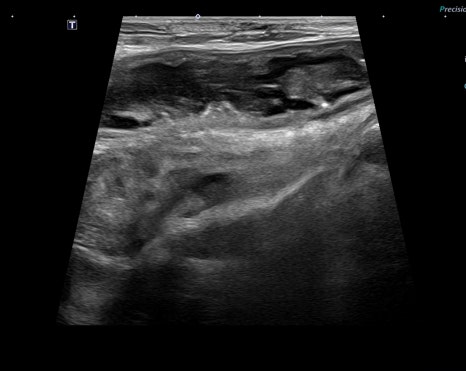

복부 초음파: 위장염, 미란 소견

- 복부 초음파: 위장염, 미란 소견